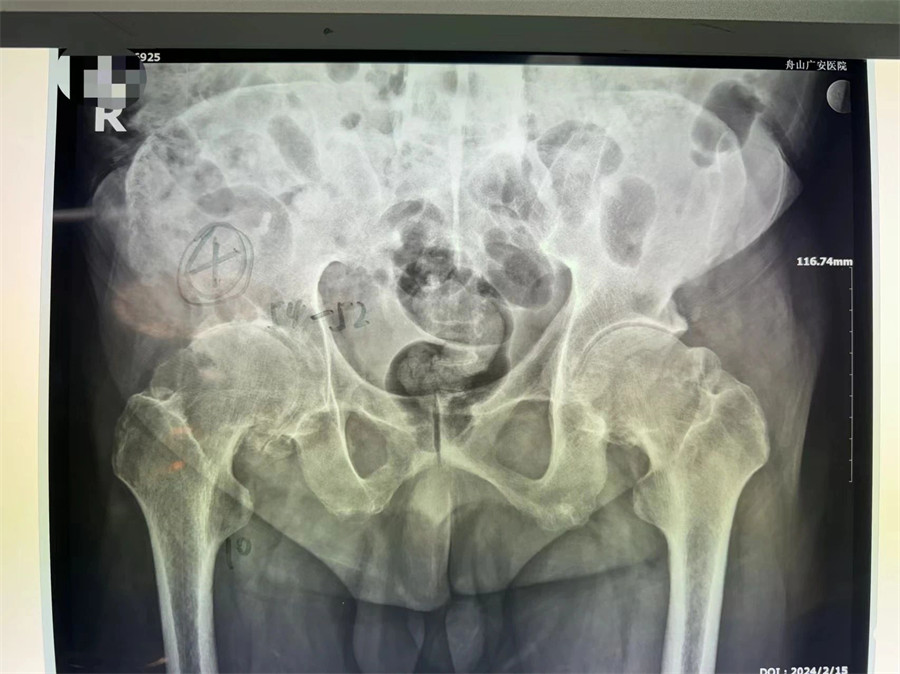

術(shù)前拍片顯示髖關(guān)節(jié)僵直伴股骨頭壞死

羅軍主任分析患者病情,認(rèn)為他強(qiáng)直性脊柱炎30年,雙髖關(guān)節(jié)強(qiáng)直,骨贅增生嚴(yán)重,嚴(yán)重影響行走功能,診斷為強(qiáng)直性脊柱炎,雙側(cè)髖關(guān)節(jié)骨關(guān)節(jié)炎晚期。治療方案只有人工髖關(guān)節(jié)置換這一種選擇。因患者的頸腰椎已經(jīng)完全融合,手術(shù)和麻醉都是一個(gè)不小的挑戰(zhàn),羅軍主任帶領(lǐng)關(guān)節(jié)置換團(tuán)隊(duì)協(xié)同麻醉科團(tuán)隊(duì),經(jīng)過嚴(yán)密細(xì)致的討論,與患者及家屬充分溝通交流后,決定行機(jī)器人輔助DAA入路全髖關(guān)節(jié)置換術(shù)。機(jī)器人輔助加微創(chuàng)置換,為這項(xiàng)高難度手術(shù)提供了有力支撐。